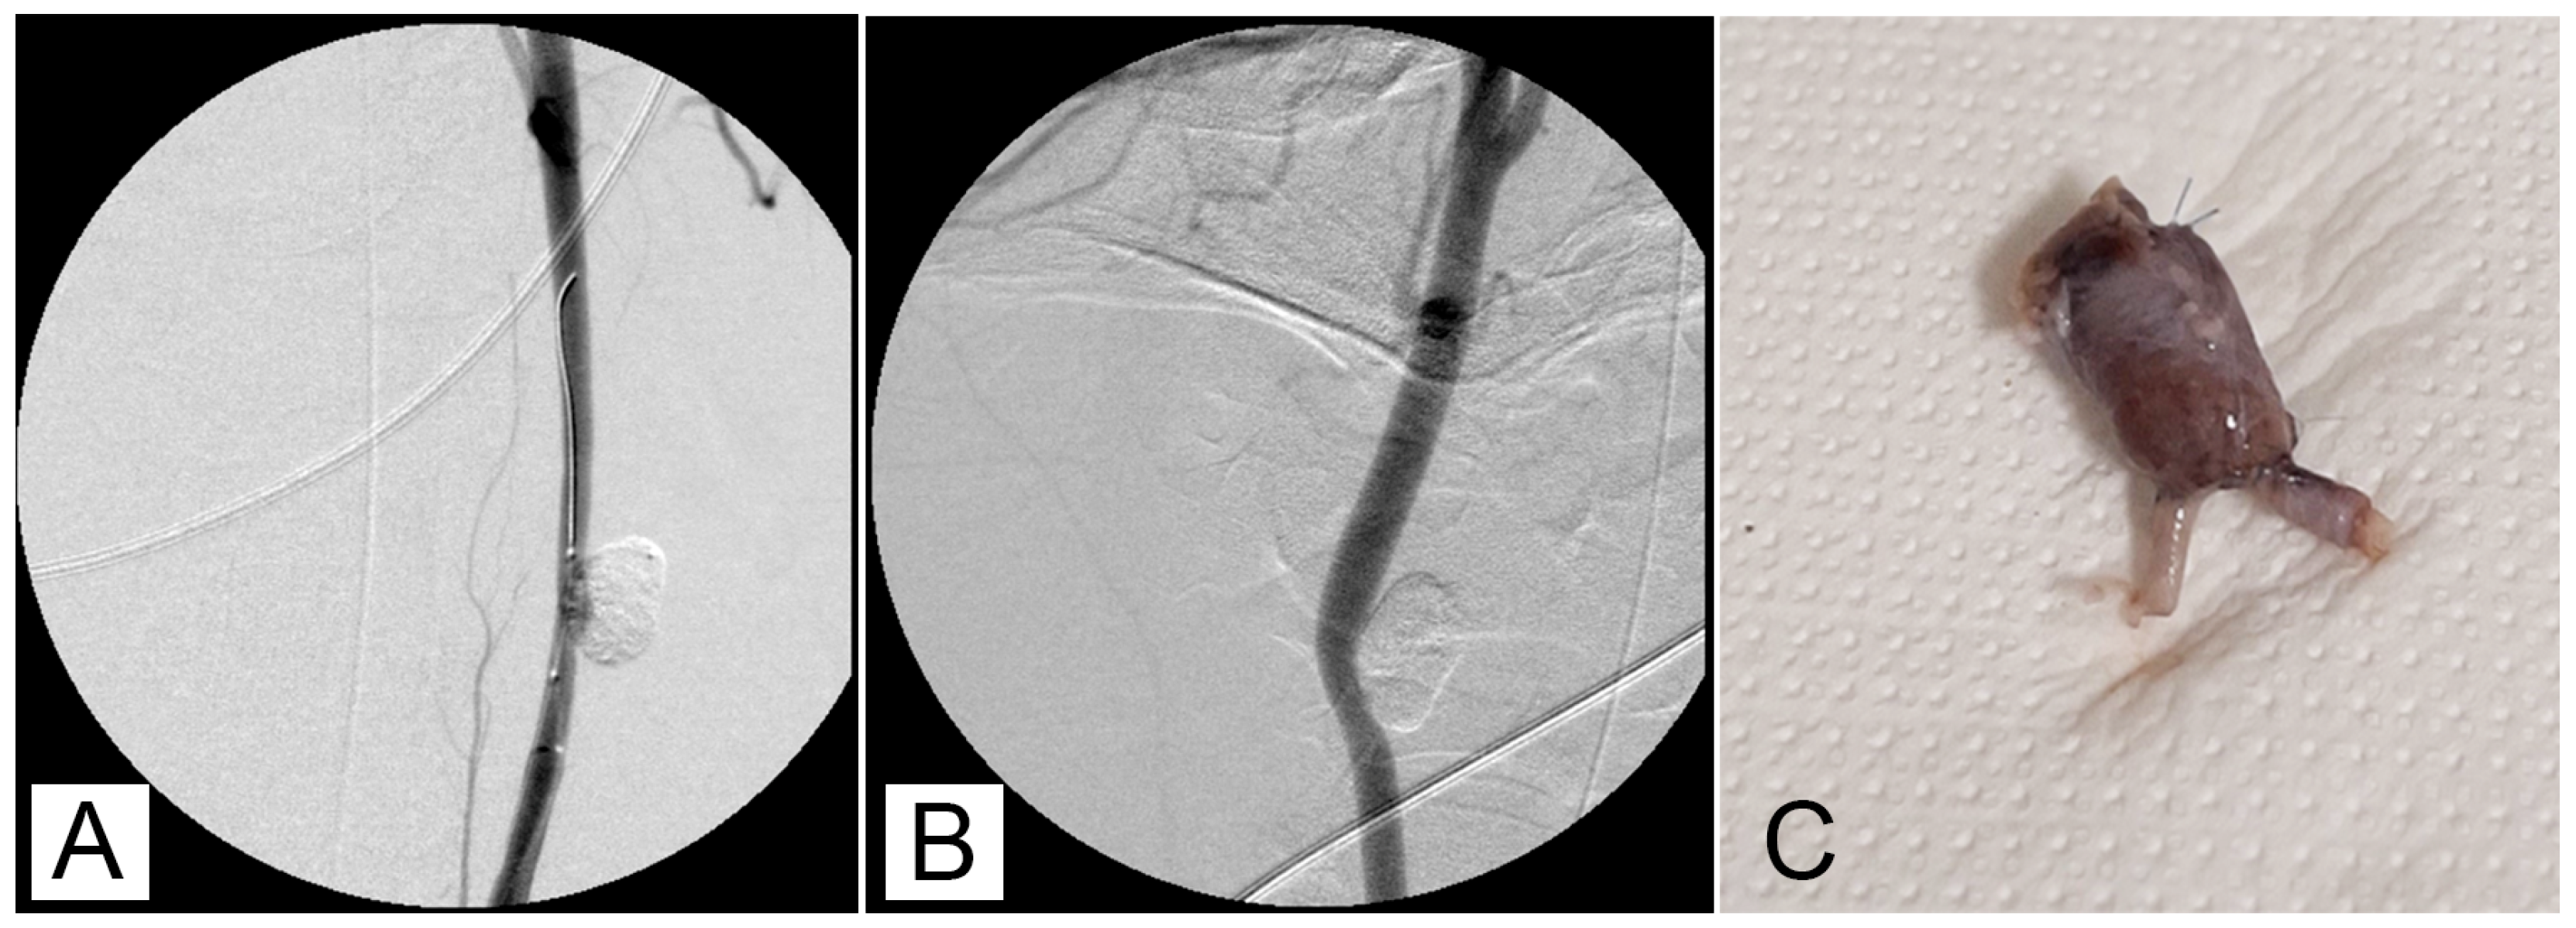

Vascular integrity of the aneurysm wall was observed in all experimentally induced defects, and no evidence of the perivascular extravasation of embolic material was detected in any specimens. An acute inflammatory reaction characterized by the presence of hemorrhages was detected in all samples resected after a few hours (t0) and 7 days post-surgery (Figure 4A). In samples collected after 7 days post-surgery, angionecrosis demonstrated by the alteration of elastic fibers was also observed (Figure 4B). At 30 days post-surgery, the aneurysm wall was slightly thickened due to the proliferation of a poorly differentiated connective tissue and the presence of chronic vascular inflammation (Figure 4C). In the aneurysm wall, scattered foreign body reactions at the periphery of embolizing material residues characterized by the presence of foreign body giant cells were also detected (Figure 4D). At the periphery of the aneurysm wall, there was edema and host tissue which showed reduced inflammatory infiltration (Figure 4E). Ninety days post-surgery, the aneurysm wall was thickened and consisted of well-differentiated connective tissue (Figure 4F). Pigment deposits of hemoglobin origin (both hemosiderin and hematin) were also observed.

Figure 4. Aneurysm walls at different times after embolization: A and B, after one week, C and D, after 30 days, and E and F, after 90 days. (A) Aneurysm wall one week after embolization, with an acute inflammatory reaction with widespread hemorrhages and a diffuse presence of neutrophils (H-E, bar = 50 μm). (B) Aneurysm wall one week after embolization, with the alteration of elastic fibers in the aneurysm wall (Orcein stain, bar = 100 μm). (C) Aneurysm wall 30 days after embolization, with thickening of the aneurysm wall due to immature connective tissue and the presence of small glue deposits delimited by a chronic inflammatory reaction (H-E, bar = 100 μm). (D) Aneurysm wall 30 days after embolization, with host tissues at the periphery of experimental aneurysm showing a reduced inflammatory reaction (H-E, bar = 200 μm). (E) Aneurysm wall 90 days after embolization; the aneurysm wall was constituted by well-differentiated connective tissue with a reduced inflammatory reaction (Masson trichrome Goldner stain, bar = 100 μm). (F) Aneurysm wall 90 days after embolization, with the absence of edema and inflammatory phenomena at the periphery of the aneurysm wall (H-E, bar = 200 μm).